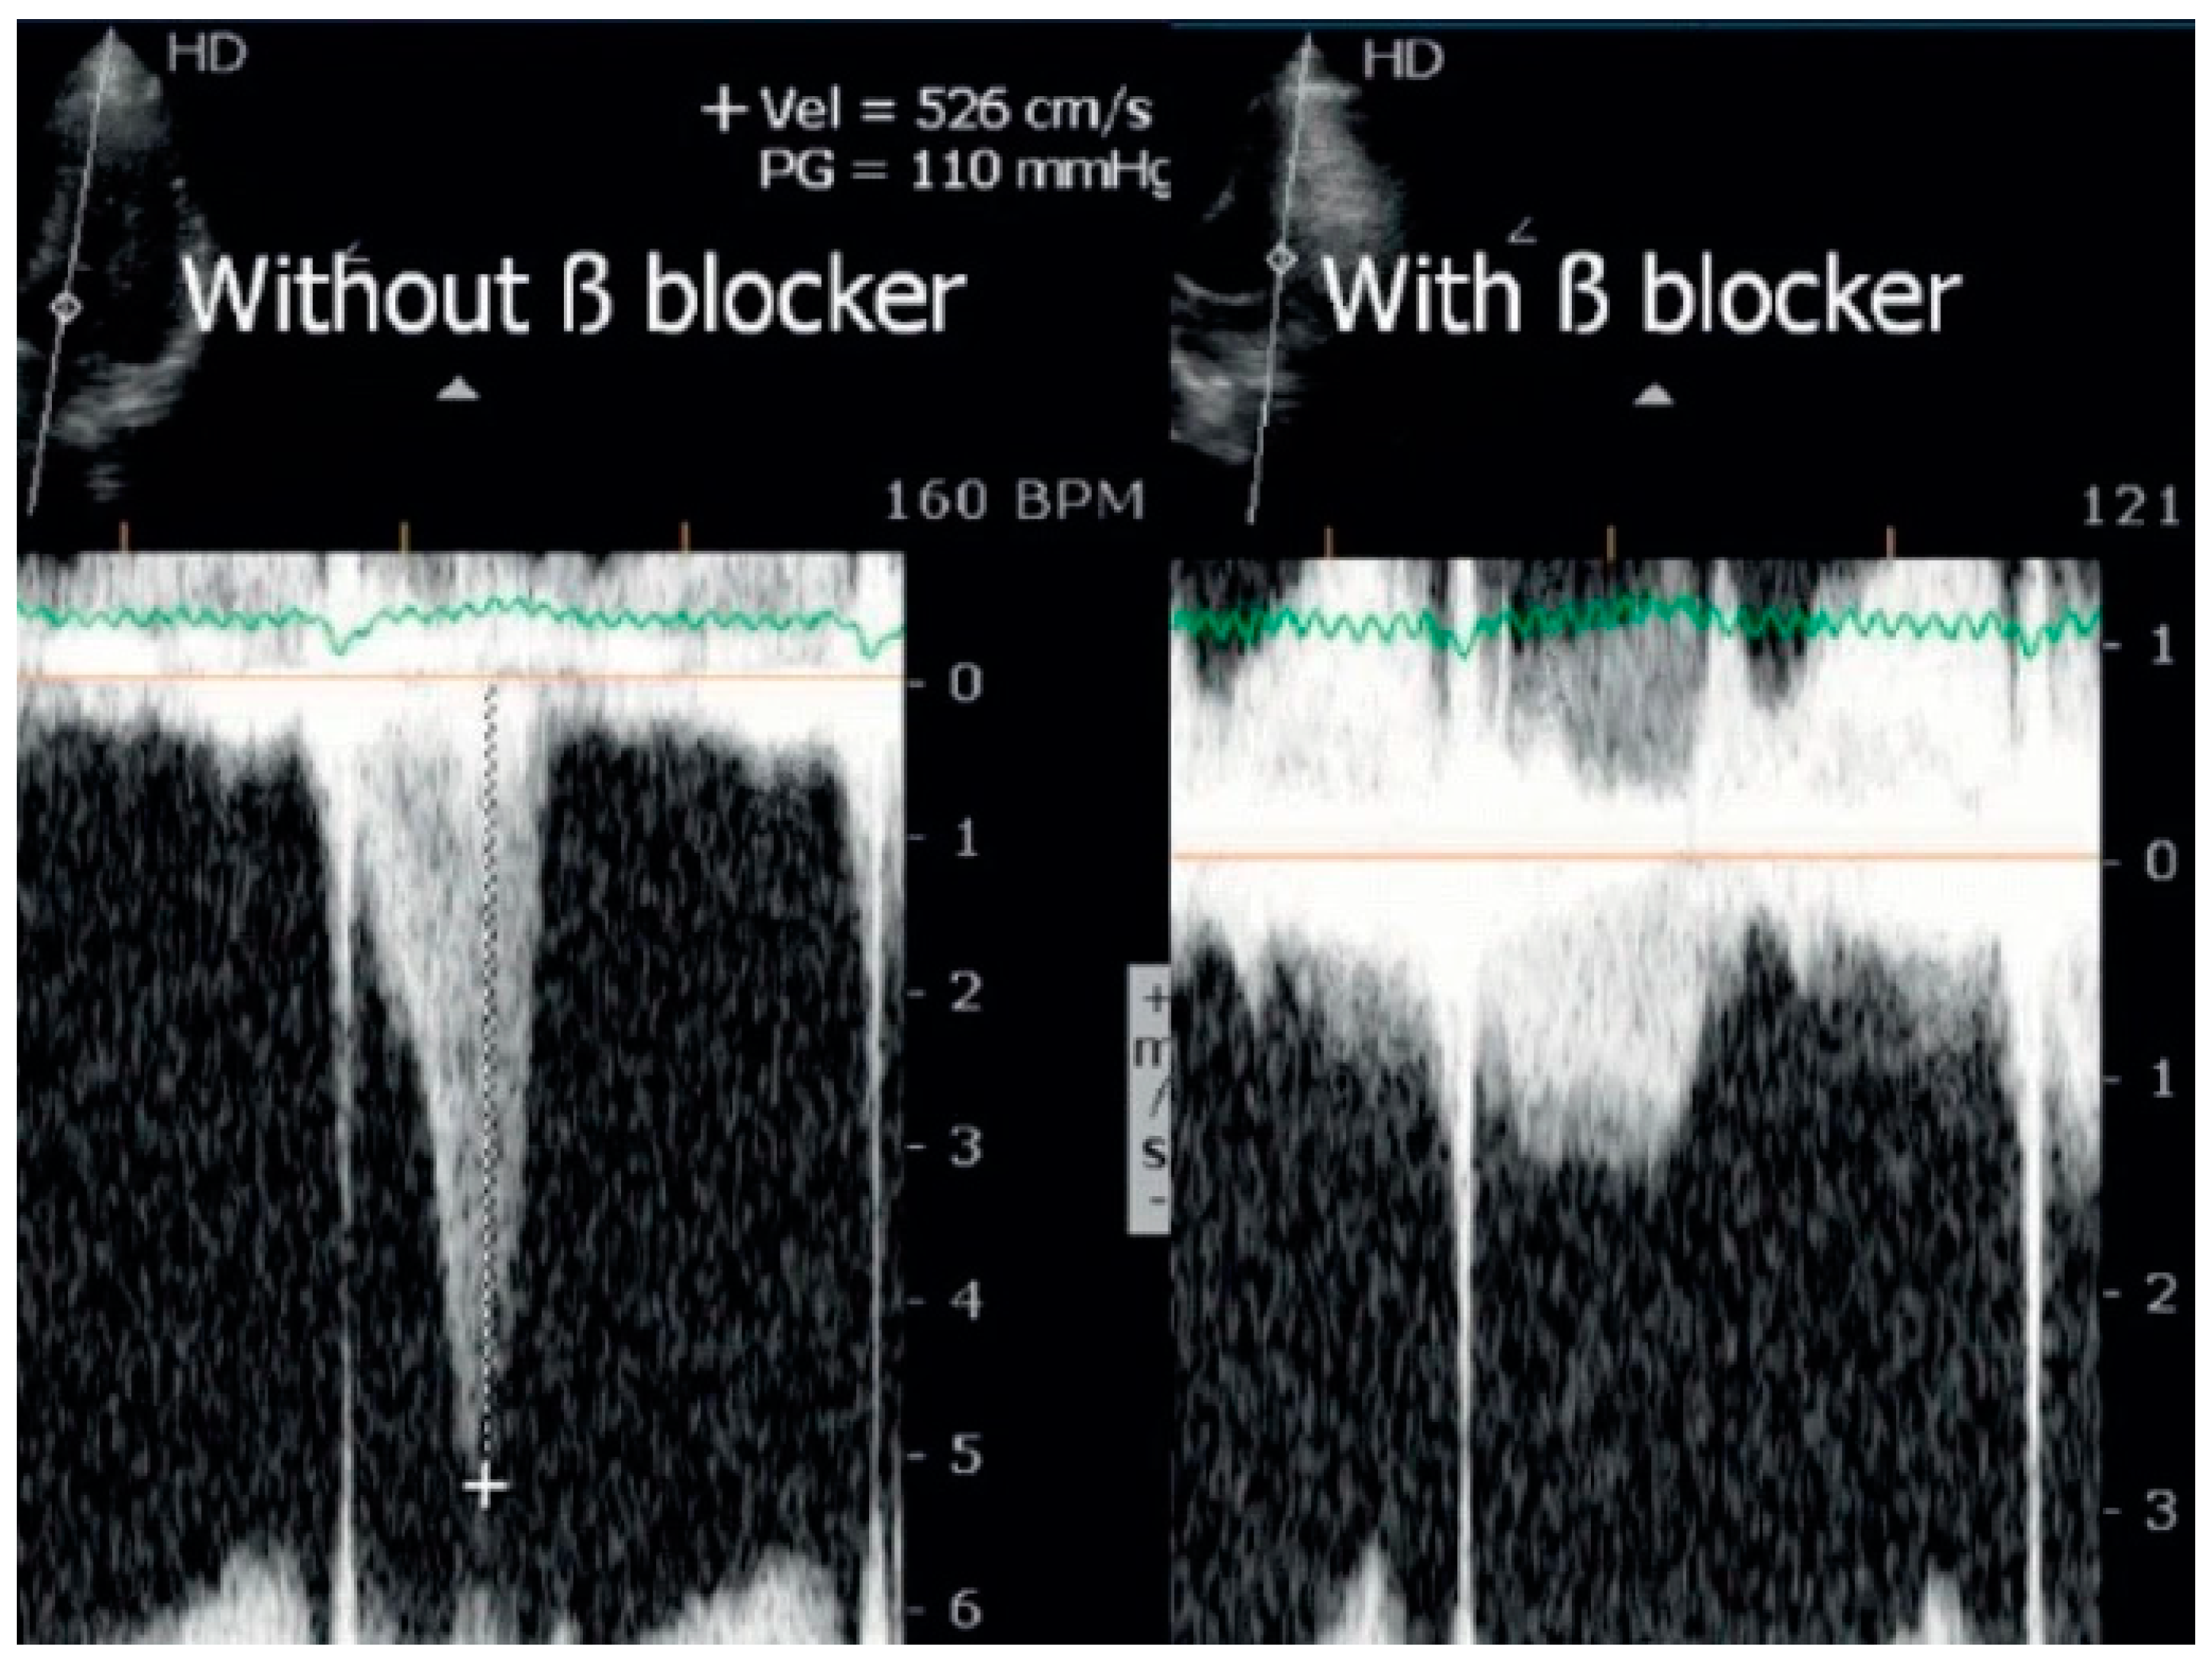

Statistical analysis was performed using the SPSS IBM Program 24 Statistics (New York, NY, USA). The summary measures are presented as mean ± standard deviation for continuous variables and counts, with percentages for categorical variables. The success rate of the methodology was 309/309 (100%). Stress-induced RWMAs were present in only two children, one with HCM and the other with normal coronary arteries (a coronary computed tomography angiography (CCTA) was performed that revealed no obstructive epicardial coronary artery disease). A significant orthostatic exercise-induced IVG (Figure 2) (>30 mmHg) was present in 101 (39%) of the 258 children evaluated due to exercise-related symptoms, alterations in the ECG, or positive stress ECG (Figure 3) and considered as candidates for beta-blocker therapy [1].

Figure 2.

Significant intraventricular gradient in a young boy with angina and ST alterations in the exercise stress test. He also developed systolic anterior movement (SAM) of the mitral valve [1].

In the evaluation of children with known or suspected heart disease stress, echocardiography is underused when compared to the adult population. For adults, there are clear guidelines that should be followed for the proper use of stress echocardiography [25,26,27,28]. On the other hand, there are no clear recommendations regarding the use of ESE in the pediatric population, and some of those who consider the use of stress echo focus on the limitations [28] instead of the advantages, such as being free of radiation, medications, and iodine-based contrast. From an ethical standpoint, the utilization of CT scans and other diagnostic procedures involving radiation in pediatric patients warrants careful consideration. While these procedures offer significant medical benefits, they also carry inherent risks, notably the potential for radiation-induced cancer. Concerns arise particularly in children due to their heightened radiosensitivity and the possibility of higher radiation doses [29]. In accordance with this concern, obtaining informed consent from both parents and children becomes imperative, depending on the latter’s age and comprehension abilities. This consent should follow a comprehensive discussion, including details regarding the recommended diagnostic examination, its associated risks and benefits, as well as alternatives. Research indicates that children aged 10 and older typically possess sufficient understanding to provide assent when presented with relevant information [16]. Additionally, discussions should cover alternative diagnostic methods and their associated risks, as well as the potential risks of forgoing the examination [30]. Numerous studies indicate that CT scans in children may result in cumulative radiation doses of approximately 50 mGy, potentially tripling the risk of leukemia, while doses around 60 mGy may similarly elevate the risk of brain cancer. Despite the relatively low absolute risks of these cancers, they remain significant. For instance, within a decade following the first scan in children under 10, an estimated excess of one case each of leukemia and brain tumor per 10,000 head CT scans may occur [31]. The aforementioned authors stress the importance of ensuring that the clinical benefits of CT scans outweigh these small absolute risks. It is advised to keep radiation doses from CT scans as minimal as possible, with consideration given to alternative procedures that do not involve ionizing radiation, where appropriate. In the present study, we show the experience of a group of “adult” specialized cardiologists with significant experience in this field (more than a mean of 500 stress echocardiograms every year during the last 20 years (1760 exercise stress echocardiograms in 2023) performing exercise stress echocardiography in a group of children. The evaluation of chest pain related or not to exercise in pediatric age, beyond clinical evaluation, is usually studied with an electrocardiogram, exercise stress test [32], transthoracic echocardiogram, 24 h Holter, and, more recently, with exercise stress echocardiography, nuclear medicine, cardiac magnetic resonance, and coronary computed tomography angiography [1,33]. A significant effort was made in the last twenty years to attain a rational use of resources (in this case, exams to study children with symptoms) [34,35,36,37]; for example, the exercise stress test (without echo) rarely helps to make conclusions about the etiology of symptoms, such as chest pain, presented by children. We underline that beginning the diagnostic approach for children presenting with symptoms related to exercise with ESE permits a reduction in the use of exams with radiation [1,2] and also defines the proper treatment in a significant number of them, as exemplified by the boy in Figure 4 and Figure 5 and the boy in Figure 9 with the use of beta-blockers [38,39].

Figure 9.

Intraventricular gradient in a child assessed before and on beta-blocker therapy [39].

We also underline the fact that the ESE performed by a cardiologist with significant clinical experience permitted the reliable diagnosis of effort asthma in eight children. Comparing our study with others in the literature [2,3,4,5,6,7,8,9,10,11,12,13,14], we found significant differences in methodology, as we only utilized exercise stress echocardiography on the treadmill with permanent clinical and echocardiographic evaluation (Video S1) [1]. We looked for usual details, like RWMAs to exclude coronary disease, valvular gradients, and intraventricular gradients in HCM children; however, the evaluation of intraventricular gradients is also performed in other children by routine, including those with a normal echocardiogram. The detection of exercise-induced intraventricular gradients (IVGs) related to symptoms such as angina, tiredness, or syncope in patients with normal echocardiogram (no hypertrophy) has previously been published [1,16,40,41,42,43,44,45,46]. The association of IVGs with symptoms [1,23,24,45,46] in terms of pediatric age has been previously demonstrated, and our results, where a significant orthostatic exercise-induced IVG appeared, seem to confirm this association. The presence of IVG was considered a normal finding by only one group of investigators [40]. The results of the present study and those from other authors suggest a clear relation between IVG and symptoms [16,40,41,42,43,44], and the clinical response to beta-blocker treatment [38,39] favors this conclusion. Guidelines recommend the use of stress echocardiography in adults when available as a first-line test instead of an exercise stress test. According to our results [1,25,27,47], echocardiography in association with stress ECG should be considered in the pediatric population, since stress ECG alone may be normal or provide a false-positive result (Figure 3) in most children, as noted in our population. Also taking into account safety reasons [48], the results of our study with exercise stress echocardiography, as well as scientific recommendations [20,25,26,27,28,47], ESE should be performed if possible to clarify unexplained exercise-related symptoms.